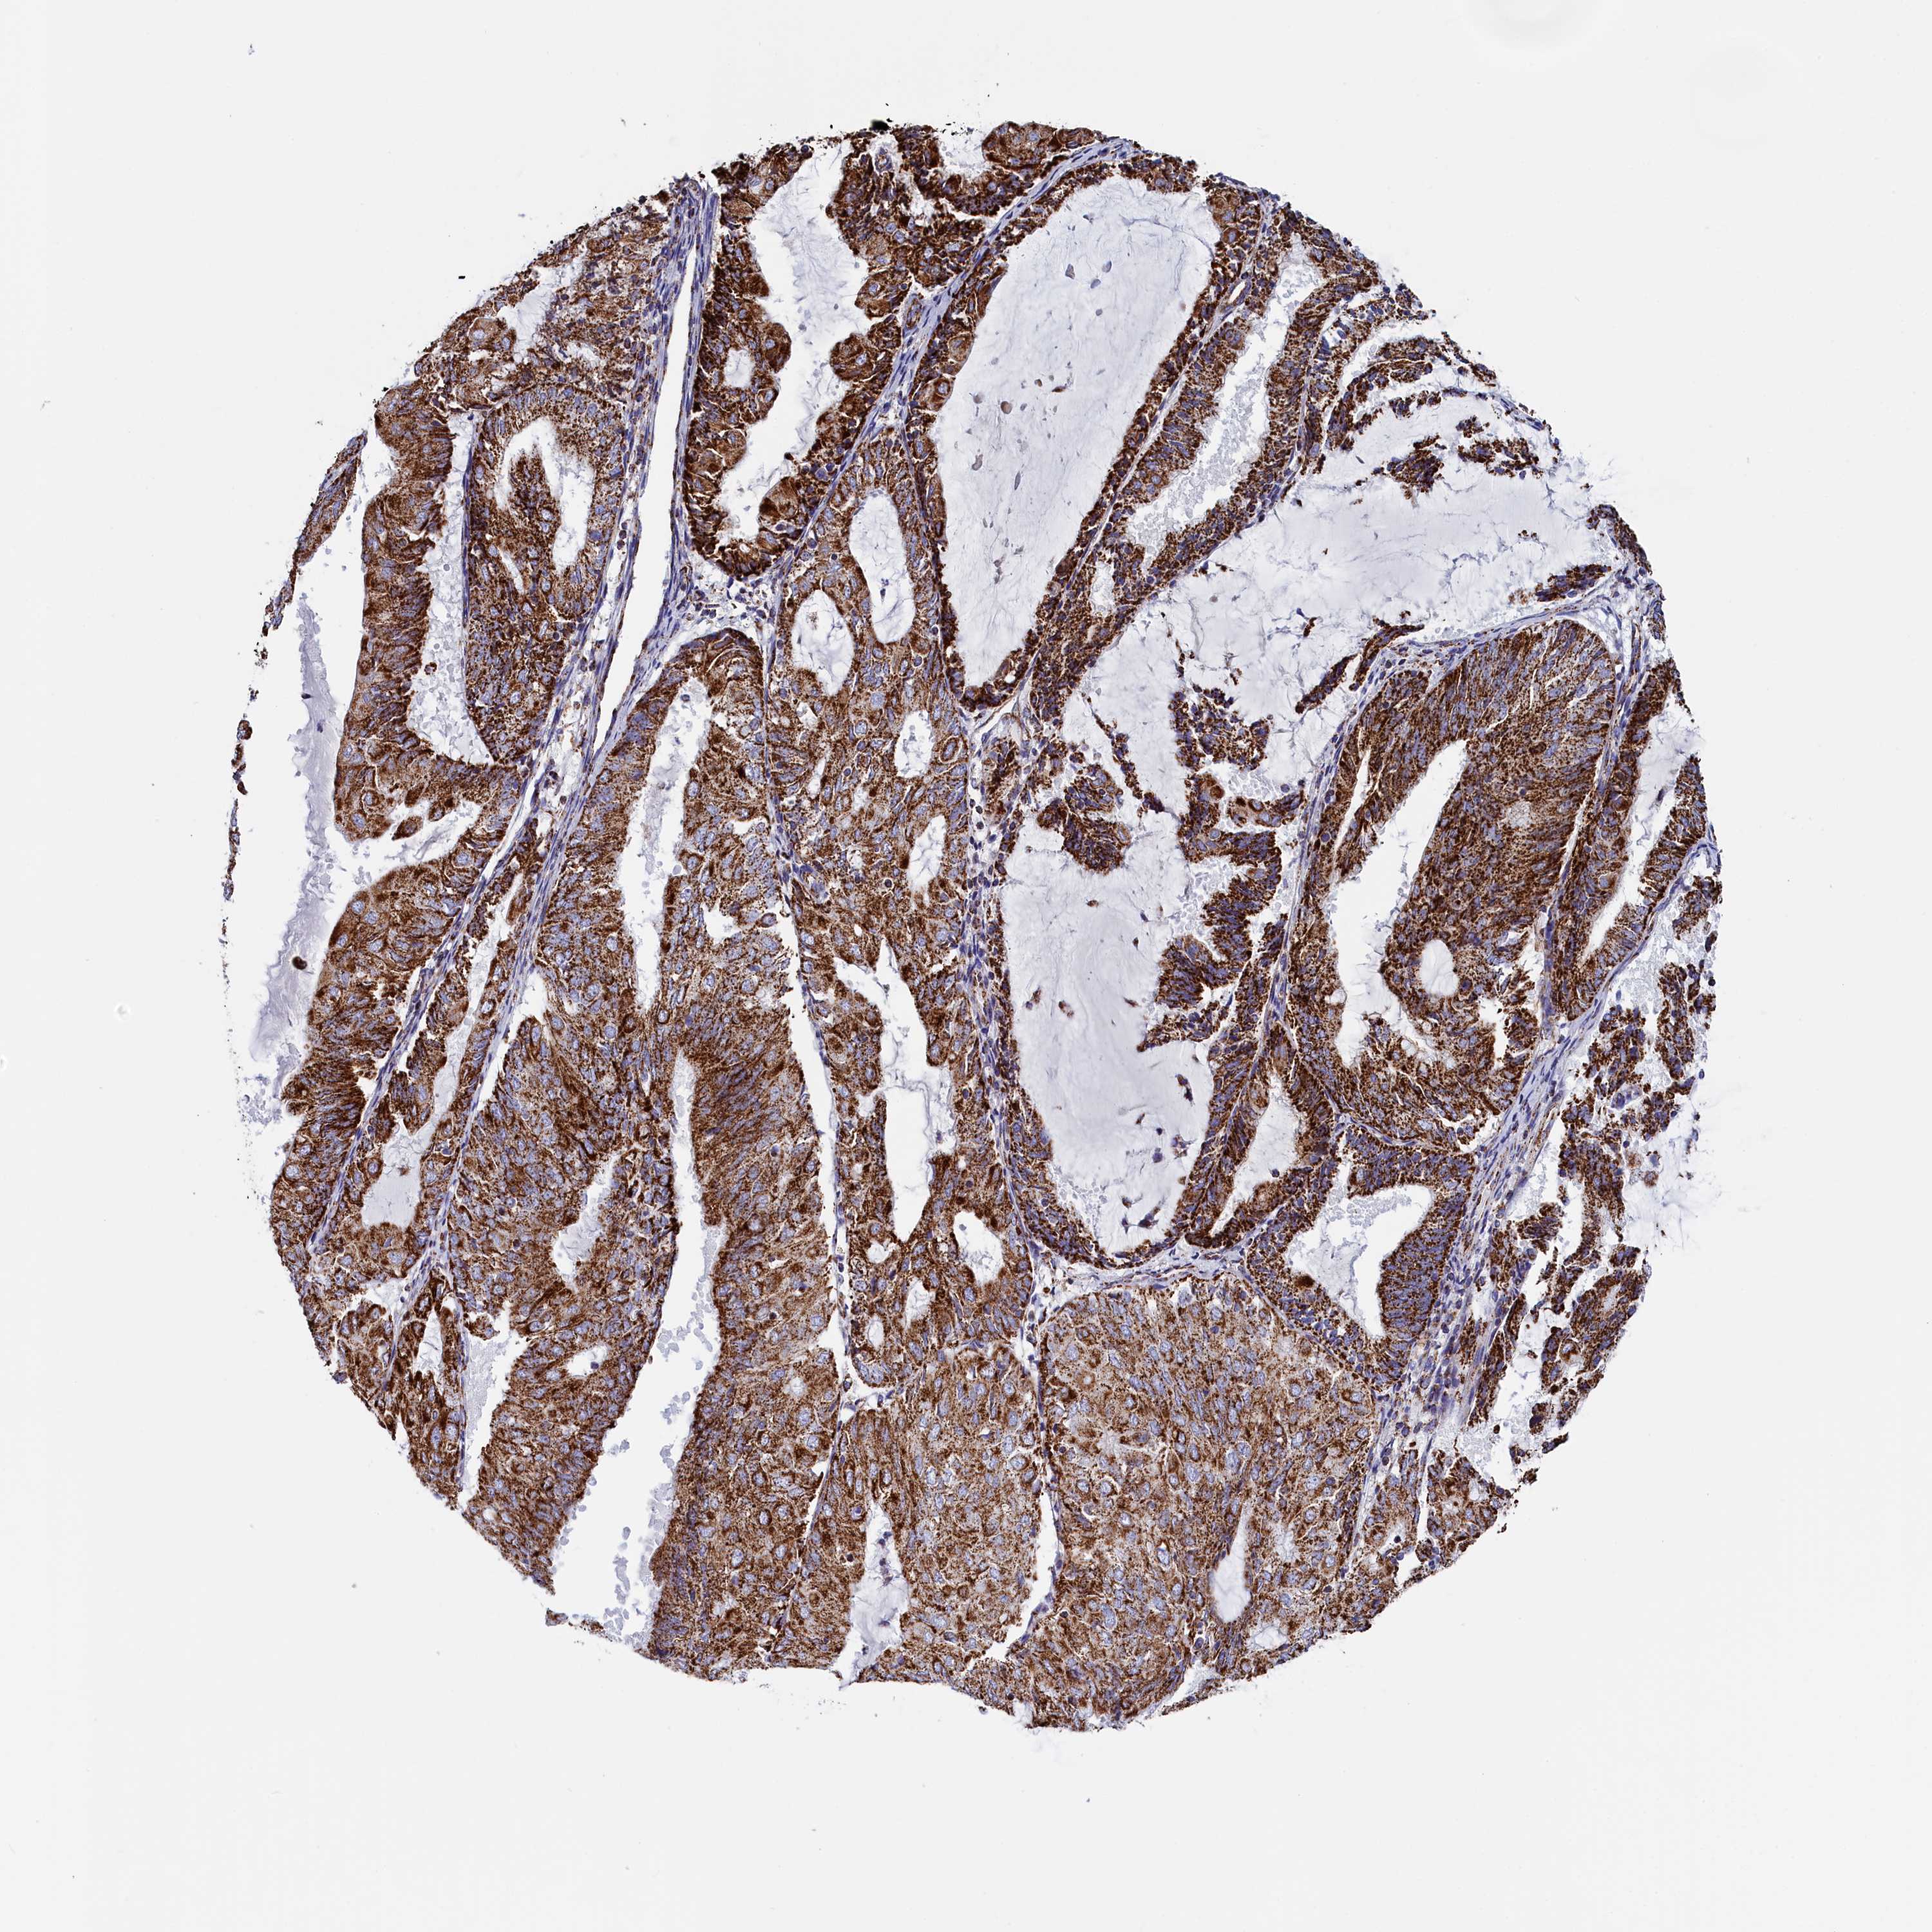

ENDOMETRIAL CANCER - Protein expressioni

A mouse-over function shows sample information and annotation data. Click on an image to view it in a full screen mode. Samples can be filtered based on level of antibody staining by selecting one or several of the following categories: high, medium, low and not detected. The assay and annotation is described here.

Note that samples used for immunohistochemistry by the Human Protein Atlas do not correspond to samples in the TCGA dataset.

Antibody stainingi

Antibody staining in the annotated cell types in the current human tissue is reported as not detected, low, medium, or high, based on conventional immunohistochemistry profiling in selected tissues. This score is based on the combination of the staining intensity and fraction of stained cells.

Each image is clickable and will lead to virtual microscopy that enables deeper exploration of all samples and also displays staining intensity scores, fraction scores and subcellular localization as well as patient and tissue information for each sample.

Antibody HPA042139

Antibody HPA058526

Staining

High

Medium

Low

Not detected

Intensity

Strong

Moderate

Weak

Negative

Quantity

>75%

75%-25%

<25%

None

Location

Nuclear

Cytoplasmic/membranous

Cytoplasmic/membranous,nuclear

Adenocarcinoma, NOS

Carcinoma, NOS